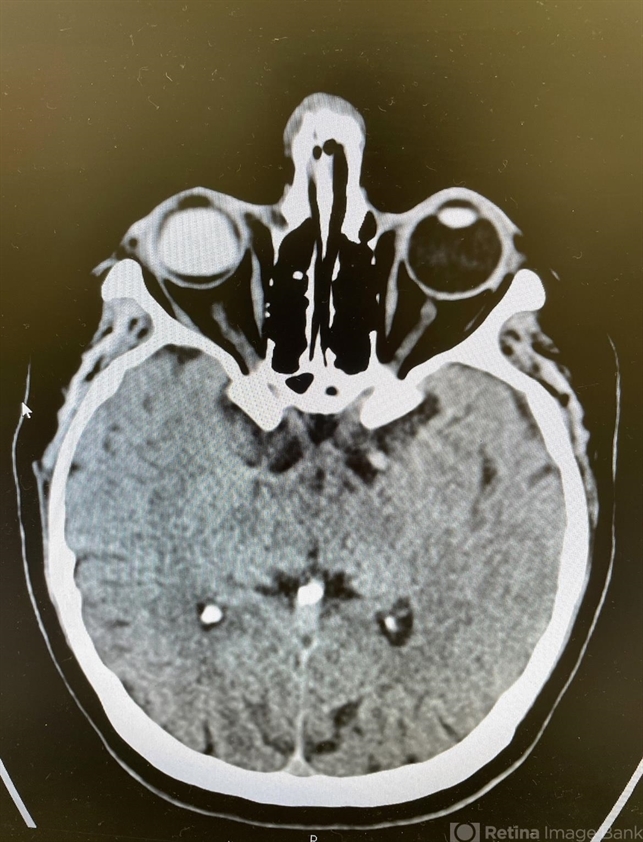

- An 65-year-old woman was taken to the Emergency Department after a fall. CT brain imaging demonstrated a well-defined, homogenous, hyperdense mass in the posterior segment of the right eye. Detailed history revealed previous vitreoretinal procedures for multiple retinal detachments. Ophthalmological examination confirmed presence of silicone oil in this eye.